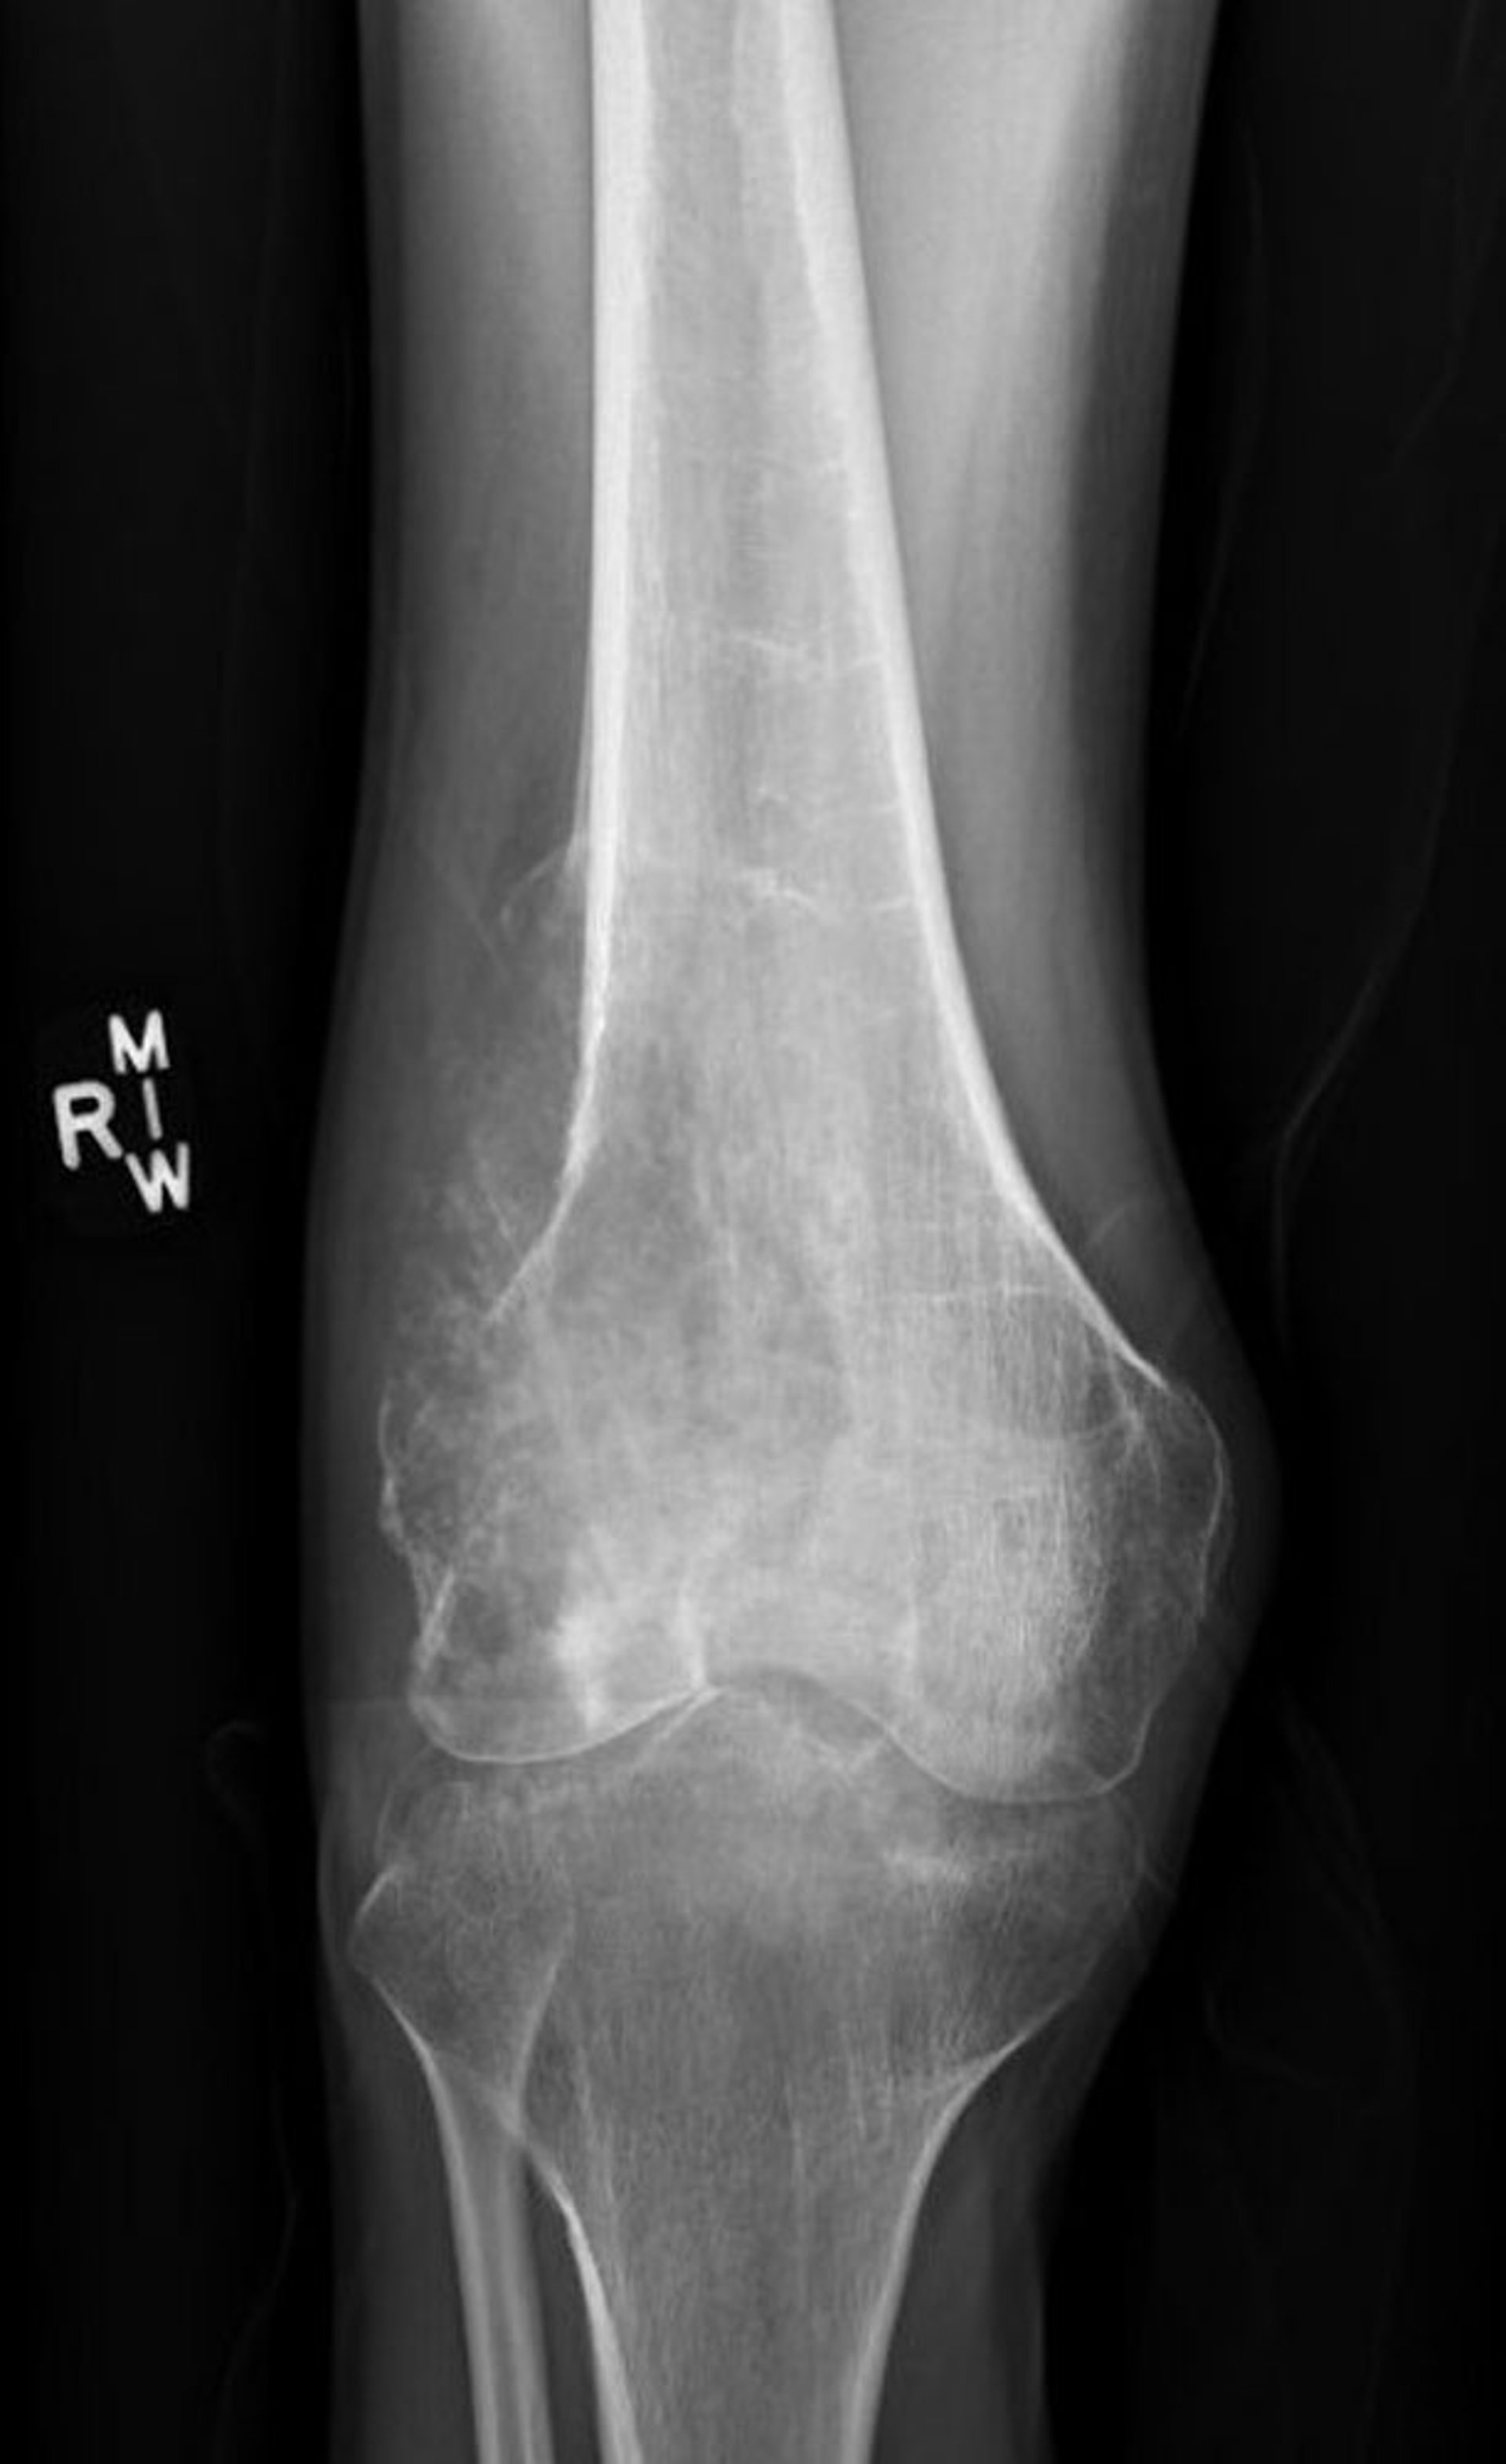

Esta radiografía de la rodilla muestra un osteosarcoma destructivo en el fémur por encima de la rodilla con apariencia lítica destructiva y el clásico triángulo de Codman que demuestra elevación perióstica patológica.

Image courtesy of Lukas Nystrom, MD.